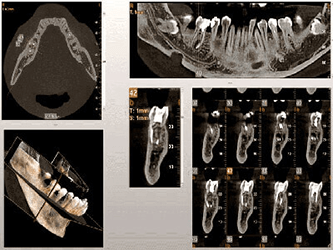

We practice the ALARA principle; (As low as Reasonably Achievable) all scans are restricted to the “Field of View” of your dentist’s prescription. It is taken using (1) pulsed x-ray exposure protocols, (2) real-time-automatic exposure control of the x-ray dose based on the patient’s actual bone density & (3) high resolution digital x-ray image sensors. These factors lead to a significant reduction in x-ray exposure equivalent to only 10% of the x-ray dose of a medical CT-Scan.

The aforementioned technology is inherent in the “myRay X9 CBCT Scan” that we use. myRay X9 is an Italian-made Oral Maxillofacial CT-Scan, certified compliant by European, Japan, USA and other international authorities in radiation safety.

Proactive Dental Management thru our 3D Imaging Manipulation Software

With Oral Maxillofacial CT Scans, your dentist enhances his ability to proactively manage your health concern thru accurate diagnosis & better treatment planning. Moreover, the patient benefits from a painless,low radiation dose CT Scan procedure.